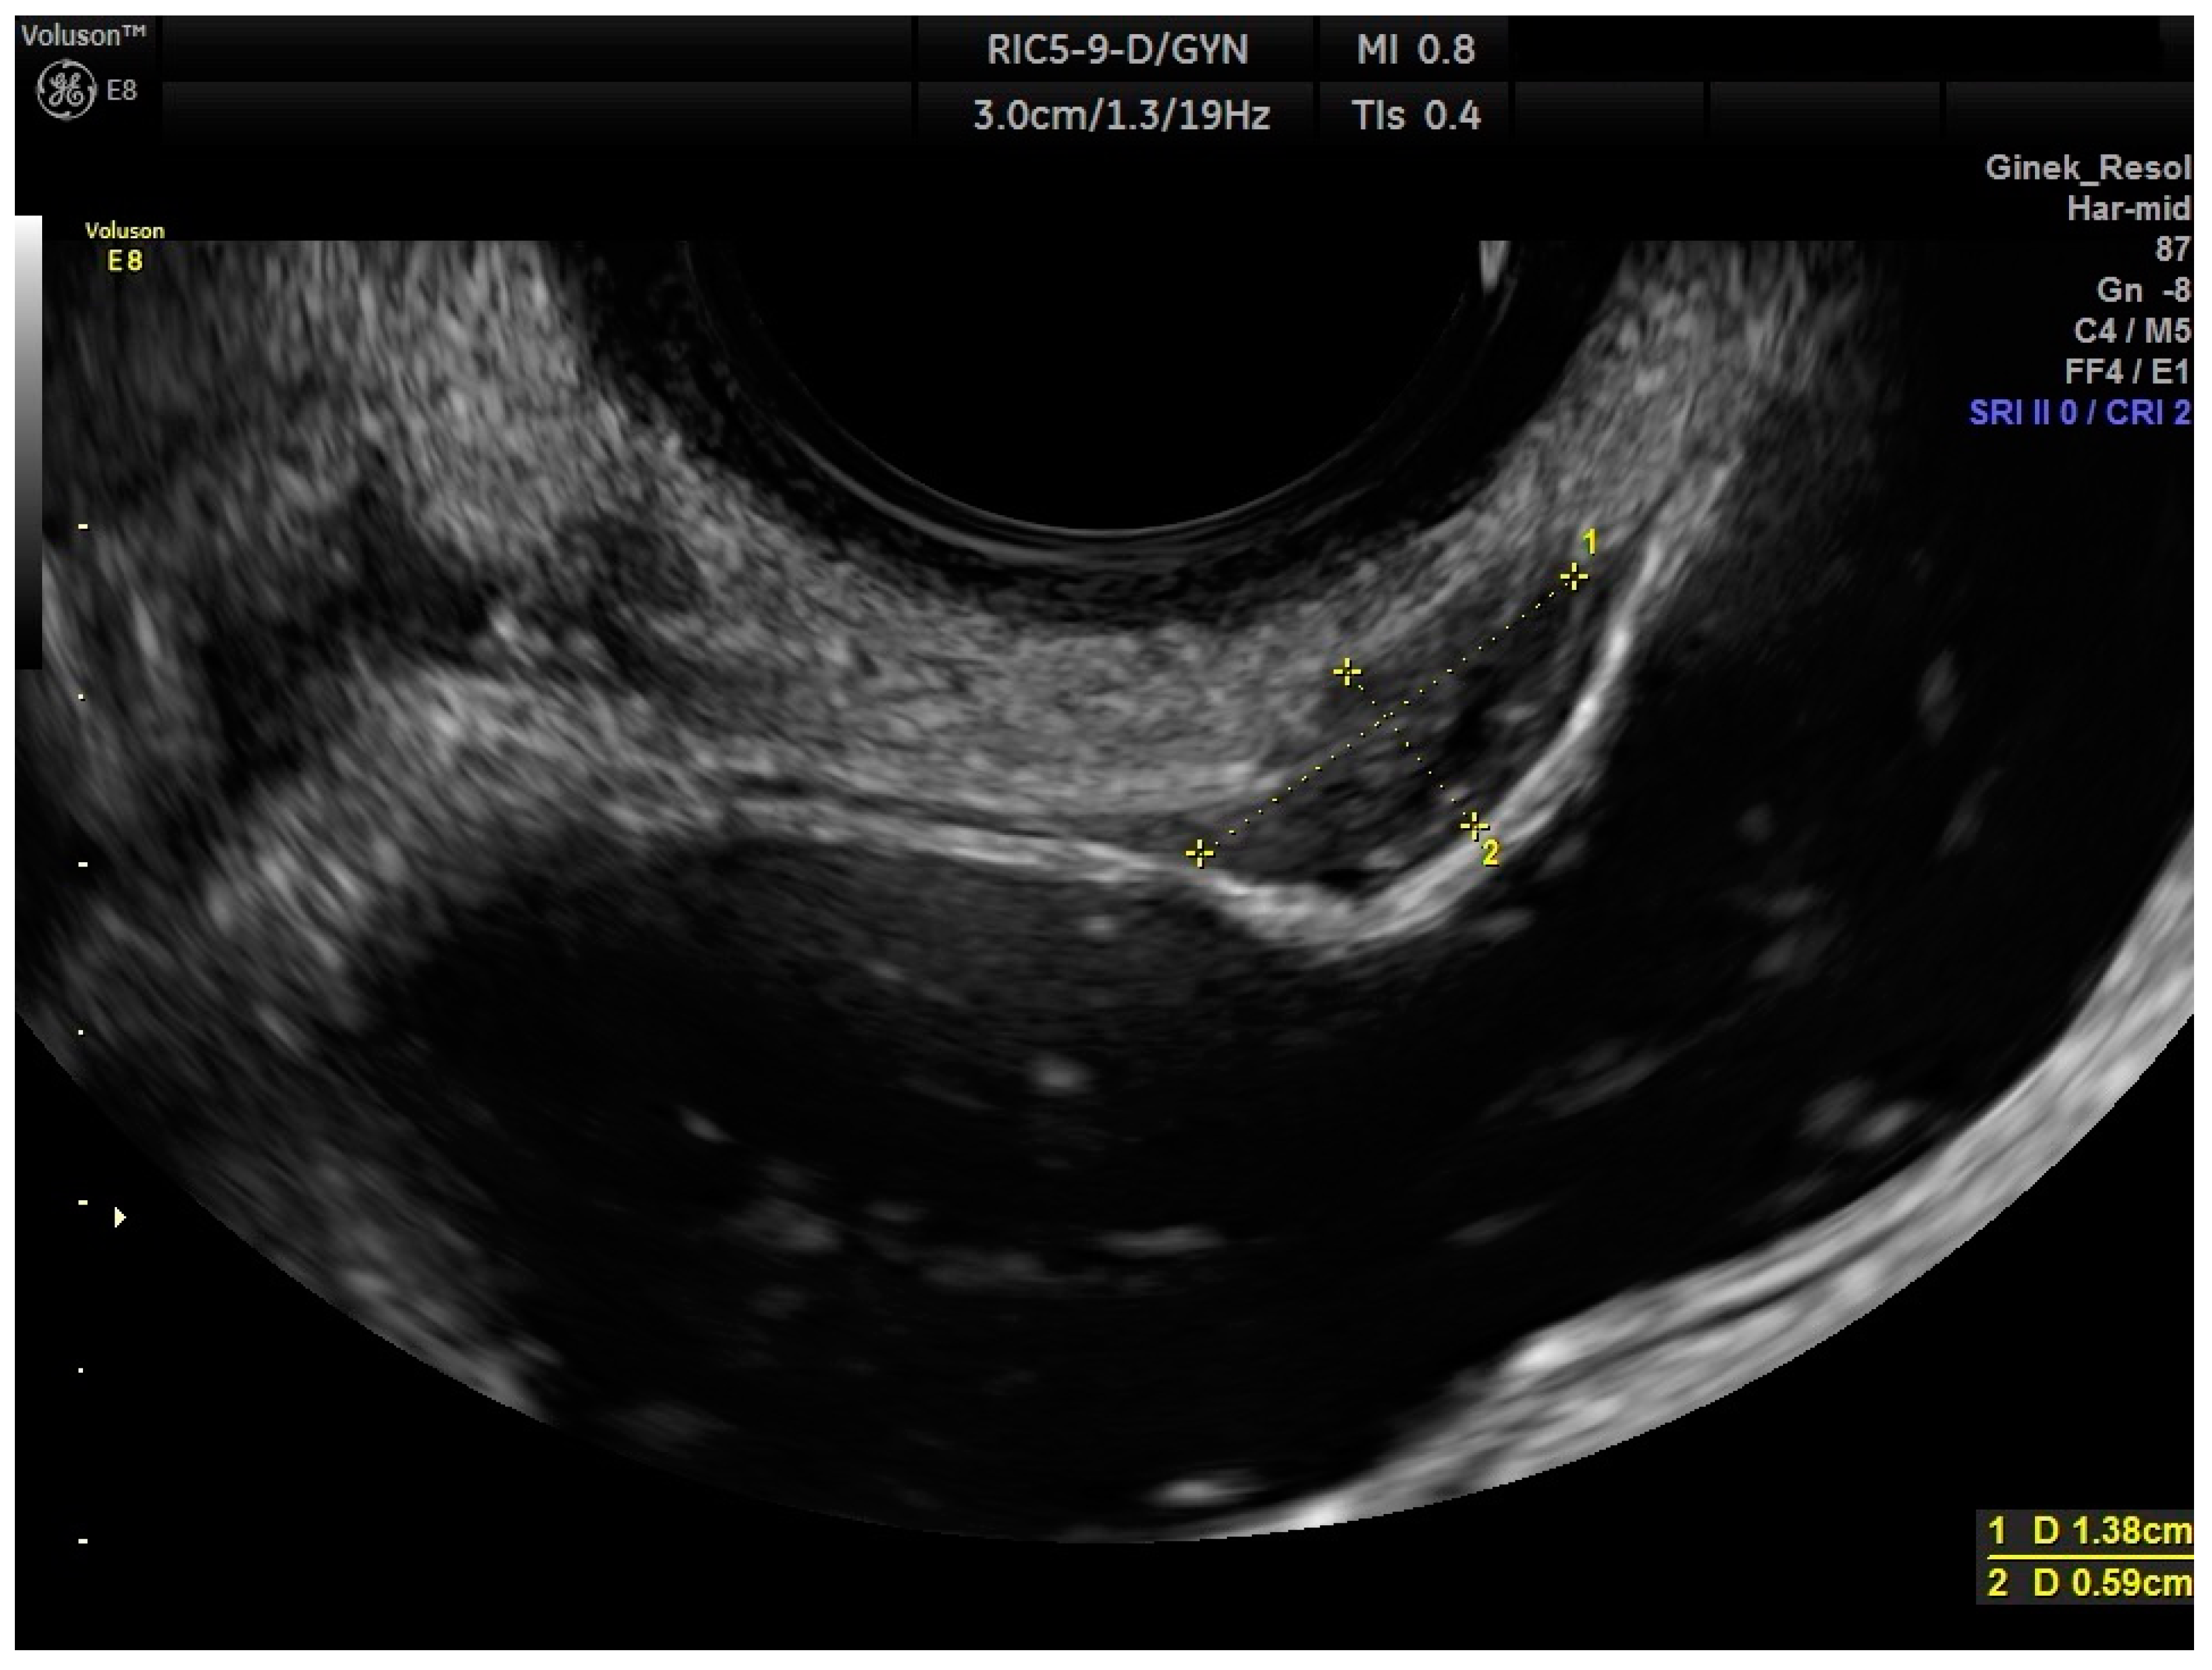

2.2. Ultrasound Measurements

| RWC-TVS greatest size (mm) | 23.613 | 0.00 | 45.00 | 9.42 | 0.94 |

| HPE greatest size (mm) | 26.033 | 8.00 | 90.00 | 18.49 |